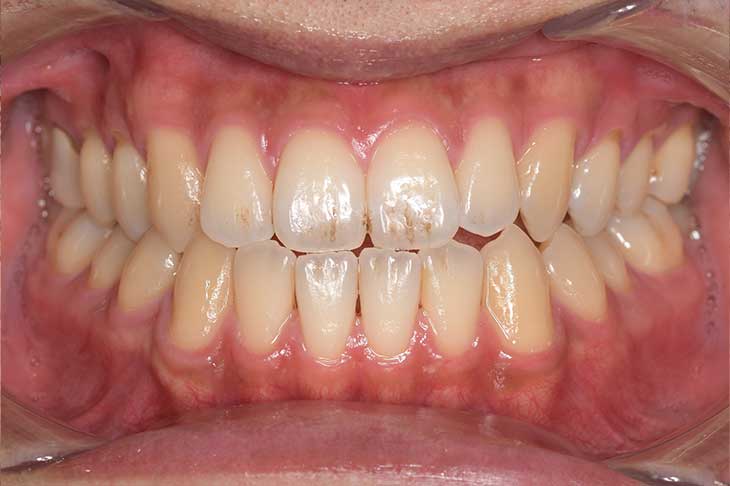

CASE 2

Before

After

基本情報

| 年齢・性別 | 30代・男性 |

| 主訴 | 歯石を取りたい |

| 治療内容 | 超音波スケーラーでの歯石除去 |

| 治療期間 | 60分 |

| 治療費 | 初診料を含め約4,500円 |

| リスク・副作用 | 歯ぐきに違和感や痛みを覚える場合がある。 1週間程度、歯を磨くといつもより出血することがある。 腫れていた歯ぐきが引き締まることで歯ぐきが下がった様に見える。 歯ぐきが下がることで歯がみしやすくなることがある。 一時的に歯の動揺(ゆれ)が増す場合がある。 |